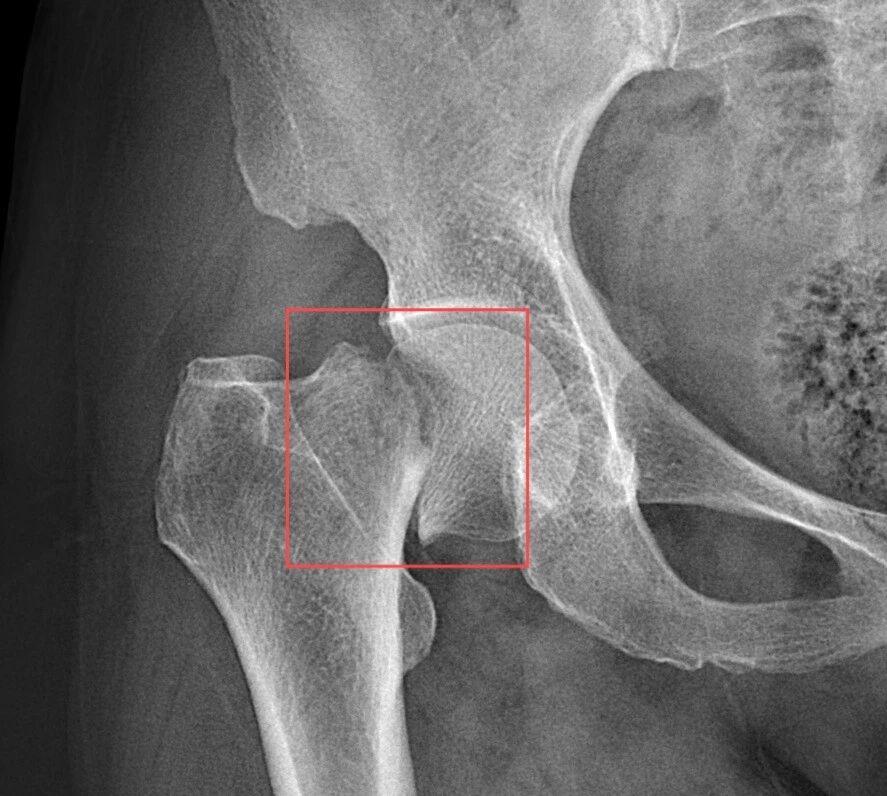

患者术前、术后CT

入院查体显示患者存在显著活动障碍,无法自主站立及行走。创伤中心(骨科)接诊后,确诊为右股骨颈骨折(Garden IV型),鉴于其病情复杂程度较高,立即启动包含创伤中心、麻醉科、心内科、综合内科、介入手术室等相关科室的多学科联合会诊(MDT)。医院副院长、云南省“兴滇英才支持计划”医疗卫生人才张锡光教授作为骨外科首席专家,全程参与病例研讨并细致听取诊疗汇报。

张锡光教授带领创伤中心(骨科)团队随即组织专项床旁查房。经系统查体及辅助检查综合研判,发现患者除原发骨折外,右下肢深隐静脉血栓,同时合并I型呼吸衰竭、肺动脉高压及窦性心动过缓等多系统危重症状。经多维度评估,该病例被列为围术期极高危患者,存在重大手术风险。

面对这一危及老年患者生命质量的严峻挑战,张锡光经过系统评估患者年龄及生理特征后明确指出,患者所患右股骨颈骨折(Garden IV型,属极高移位型骨折),若采取保守治疗或常规内固定手术,不仅存在骨折端难以愈合、股骨头血供中断性坏死的风险,更将因长期卧床导致肌肉系统进行性萎缩、骨密度加速流失、关节活动度永久性受限等器质性损害。尤其值得注意的是,继发性肺部多重耐药菌感染、复杂性尿路感染、心功能代偿失调以及下肢深隐静脉血栓进展为致命性肺栓塞等风险,将使患者陷入多系统功能衰退的恶性循环。实施精准的关节置换术实为打破困局的关键所在,可使患者在术后48小时内实现保护性负重训练,最大限度恢复运动功能并阻断并发症链式反应。